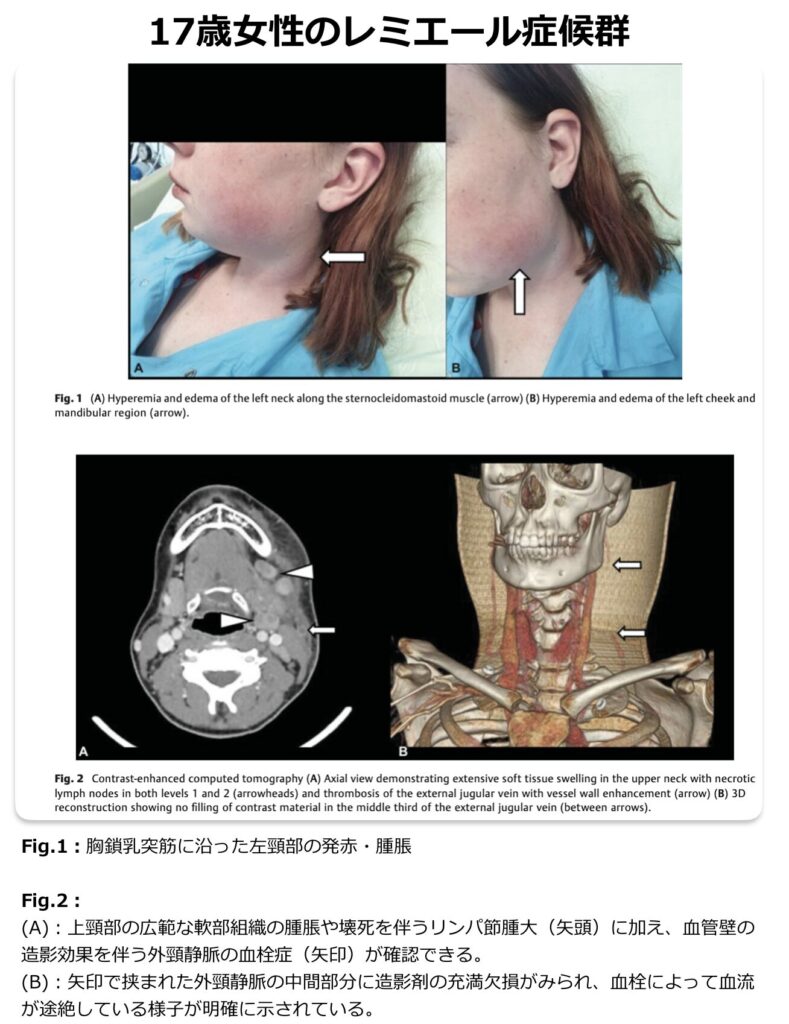

Lemierre症候群

- Lemierre症候群は、口腔や咽頭領域の感染に続発して引き起こされる、内頸静脈の化膿性血栓性静脈炎です。

- なお、Lemierre症候群の病態の主体は内頸静脈の感染性血栓ですが、炎症の波及により外頸静脈などの周囲の静脈にも血栓が生じ得るようです。

症状(左右差がありすぎる頸部所見に注意!)

- 発症初期:39℃台の高熱、頭痛、咽頭痛が主な症状です。この段階では一般的な急性上気道炎(風邪)と鑑別することが困難です。なお、初発症状として頸部腫瘤(23%)や頸部痛(20%)が多く認められます。

- 特徴的な頸部症状:静脈炎はほとんどが片側性であるため、同側(片側)の胸鎖乳突筋に沿った圧痛や腫脹が生じることが多いです。これらに加えて、開口障害や流涎などの症状が現れた場合は、Lemierre症候群を強く疑うサインとなります。

- 進行期(肺への波及):感染が進行すると高頻度で肺に遠隔感染巣を形成し、呼吸困難、胸膜炎症状、喀血などを引き起こします。具体的には、敗血症性肺塞栓による壊死性空洞病変、膿胸、肺膿瘍、縦隔洞炎といった重篤な肺合併症をもたらします。

- 造影の頸部~胸部CT検査が最も有用です。

- Lemierre症候群の診断は、血液培養検査の結果(嫌気性菌群の検出など)とあわせて、患側の内頸静脈内に血栓性病変が画像的に確認できることが一般的な決め手となります。

- 頸部エコー(超音波)検査:簡便な検査ではありますが、鎖骨や下顎骨よりも深い部位にある病変を評価するには感度が低いとされています。

- 頸部~胸部造影CT検査:診断において最も中心となる検査です。内頸静脈内の陰影欠損や血栓を的確に評価することができます。さらに、胸部まで含めて撮影を行うことで、Lemierre症候群に高頻度で合併する遠隔感染巣である肺病変(多発性の空洞を伴った結節影など)の有無も同時に確認することができます。